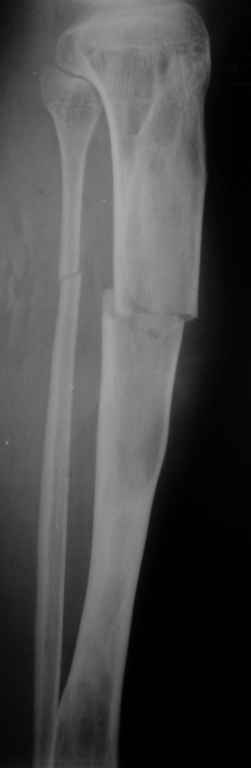

Вторая проекция.

Re: Патологический перелом костей голени.

Если это фиброзная дисплозия, зачем выполнять экскохлеацию? Это не опухоль. Достаточно провести остеосинтез (лучше БИОС). Травма стимулирует остеогенез и произойдет спонтанная оссификация в зоне перелома. Пациент прожил 20 лет без экскохлеации. При полиоссальной форме фиброзной дисплазии не принято радикально лечить один из очагов. Другие все равно останутся. В отношении дополнительной пластики высказаться затрудняюсь, может быть стоит. И если она будет выполняться, следует выполнить и биопсию содержимого полости в зоне перелома для исключения ОБК.

Костная пластика фиброзной дисплазии обречена на неудачу. Ткань фиброзной дисплазии преобладает над нормальной костью через несколько лет. Переломы при фиброзной дисплазии заживают так же, как и обычные. Так что обычного гвоздя будет достаточно. Это защитит кость от переломов в будущем. Вероятность преобразования в остеосаркому порядка 4-ёх процентов. Так что имеет смысл следить за пациентом на протяжении всей жизни.

Доброго времени суток. Всем участвовашим большое спасибо за советы и предложения. Вчера выполнили рассверливание КМК и БОИС большеберцовой кости 11 мм штифтом. С уважением, Евгений.